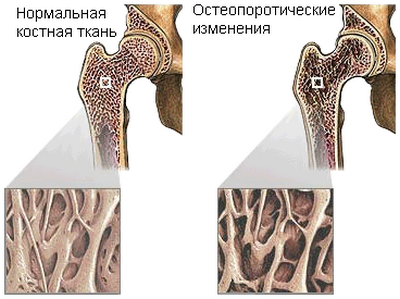

Алдымен остеопороз дегеніміз не екенін түсіндіріп өтейік. Остеопороз — сүйек тығыздығының біртіндеп төмендеуі. Кальцийдің жетіспеушілігі сүйектердің өте әлсіз болуына әкеледі, тіпті болмашы «оқиғаларда» да сынуы мүмкін. Мысалы, сәл итергенде немесе автобус кенеттен тоқтаған кезде. Остеопорозбен ауыратын адам құлап қалса, сынық пайда болады.

Өрбу жалғасын тапқан остеопороз айқын белгілерін бермейді. Әдетте, адам оны кездейсоқ біліп қалады, мысалға, қолға не аяққа жеңіл соққы алғанда сынып кетеді. Сонда ол дәрігерлерге — хирургқа, травматологқа немесе ортопедке жүгінеді. Бірақ ауруды болдырмау әлдеқайда оңай: салмақты бақылау, алкогольді, кофені, ет өнімдерін, тұзды тағамдарды азайту, энергетикалық сусындардан бас тарту.